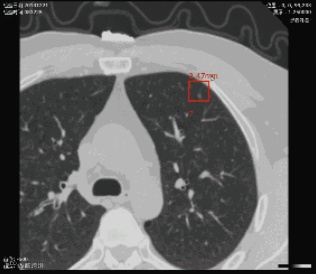

建立在医学影像诊断专家数据库基础上,通过将强化学习、深度学习等技术应用于医学影像,实现医学影像快速处理与病灶位置精确识别,予以医生诊断建议。主要应用于病理图像、眼底图像、放射、核磁等影像的快速诊断,降低医生诊断时间,减少误诊率,缓解医患矛盾;同时,探索自动影像获取技术,使一些基于实时信息的医学影像如超声图像、窥镜图像的智能识别诊断变为可能。